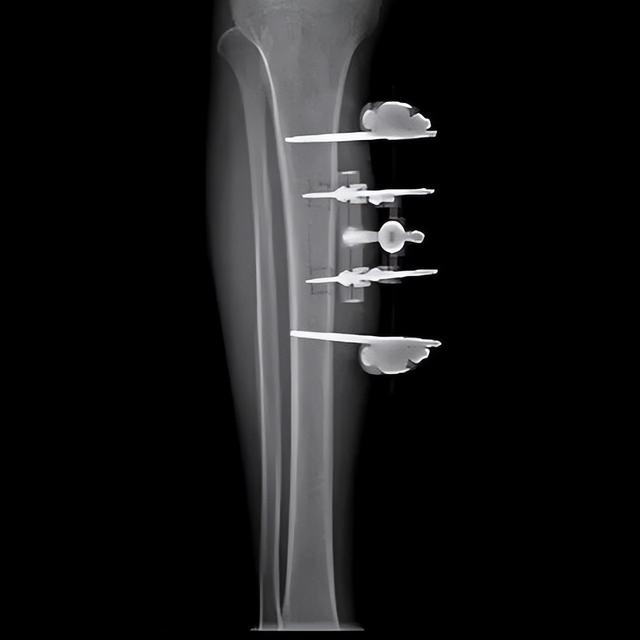

胫骨横向骨搬运手术外观